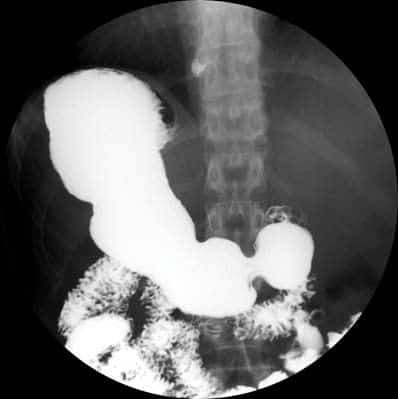

Noticias y Articulos Tránsito esofagogastroduodenal (E.G.D.) – Parte II 21 junio, 2012 Tidito Imágenes Transito Esofagogastroduodenal (E.G.D.) Seriadas Bulbares Duodeno en Anteroposterior